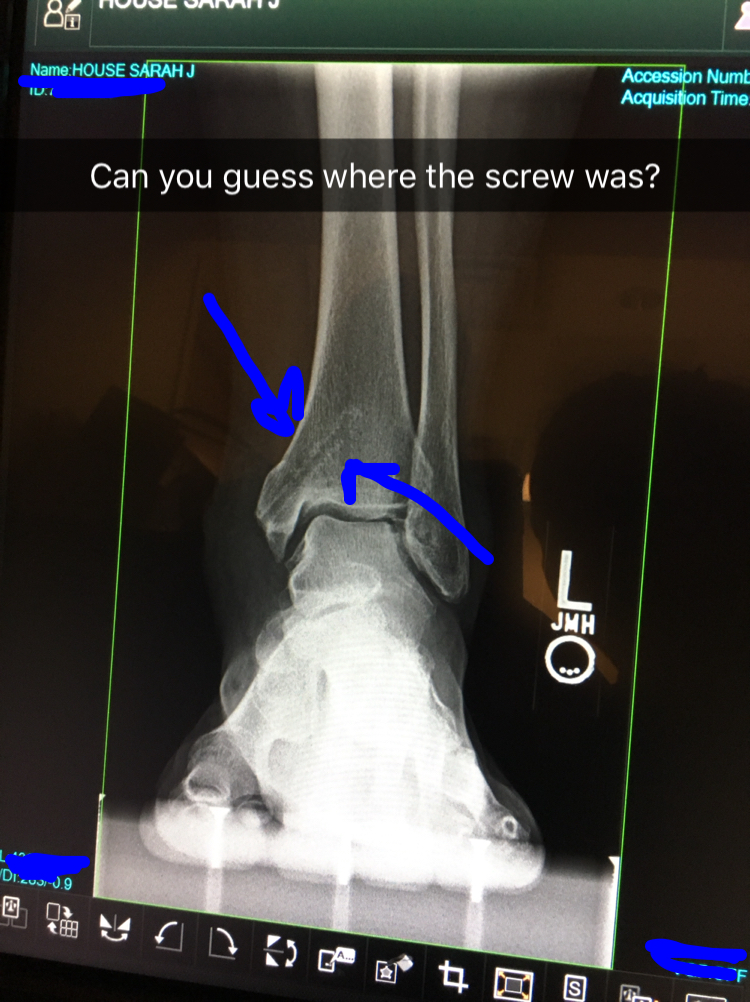

From sarahhouse365.blogspot.com

Sarah House 365 My Ankle Hardware Removal Removing Hardware From Ankle Every injury is different and everyone heals at different rates. Use ice as much as possible. Some or all of the hardware may be removed. Elevate the leg as much as possible, above heart level. It does take time to recover from the second. Sometimes, screws may break or be very hard to find. After most surgeries, the hardware causes. Removing Hardware From Ankle.

Sarah House 365 My Ankle Hardware Removal Removing Hardware From Ankle This can be done in the office or with mild sedation (twilight sleep) in. Sometimes, screws may break or be very hard to find. Use ice as much as possible. If you do have discomfort, removing the screws or plate and screws can relieve that pain. External fixators (pins and bars outside the skin) are routinely removed. Every injury is. Removing Hardware From Ankle.